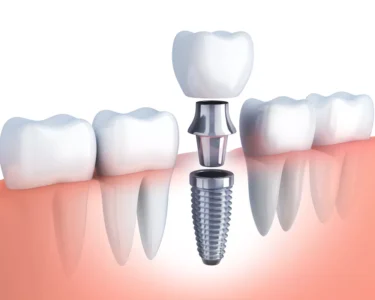

At Advanced Dental Care we believe in offering our patients what’s most appropriate from basically 3 alternative options for tooth replacement: Ideally an implant. Second choice would be “Crown and Bridge.” A less desirable, but a viable selection, would be a removable denture.

- Dental Implants